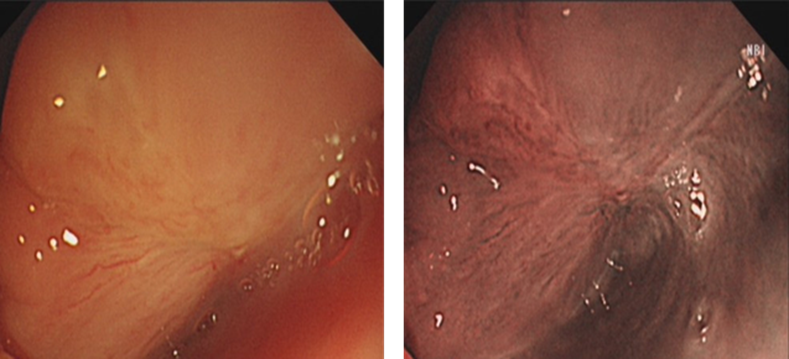

胃镜检查:环后区、梨状窝可见色泽发红、直径约1.8cm的病变,NBI下呈茶色调,边界清楚,考虑为右侧下咽部早期癌。

image.png

图1 胃镜检查结果